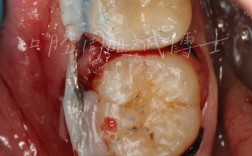

- 临床检查: 口腔检查、牙周状况评估(牙周病必须先控制!)、咬合分析。

- 控制牙周病: 必须进行彻底的牙周治疗(洁治、刮治、根面平整),确保口腔环境健康,这是长期成功的基石!

- 骨增量手术: 按照计划进行相应的骨增量手术(如GBR, 上颌窦提升,骨移植等)。

- 种植体植入手术: 在确认骨增量效果良好、骨量足够后,进行种植体植入手术。